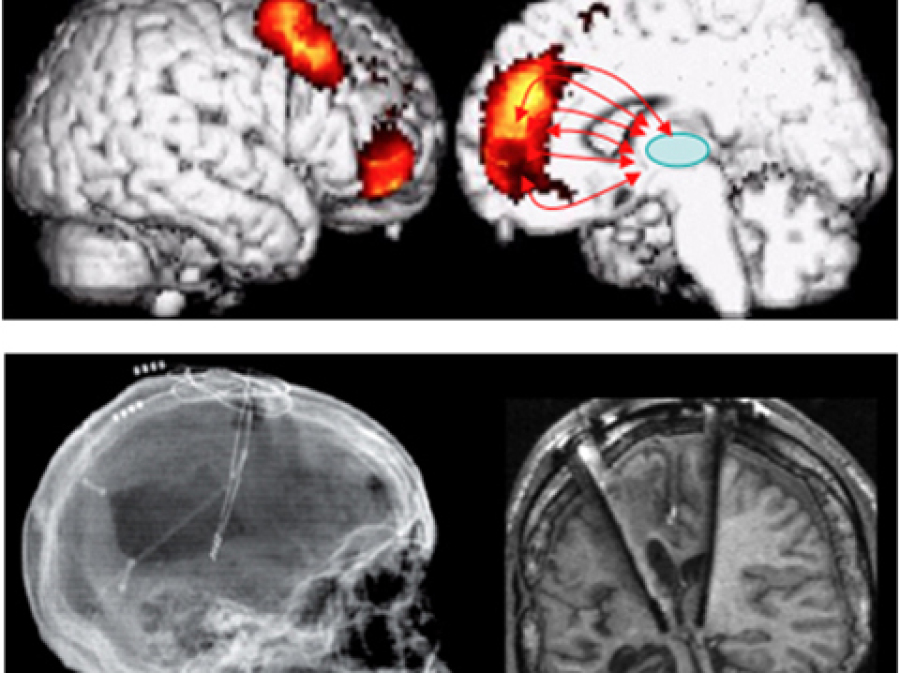

Learn MoreMovement Disorders

Parkinsonian syndromes, dystonia, tremor, chorea, tics, myoclonus, cerebellar disorders and others

Learn MoreTransient Loss of Consciousness

Epilepsy management, syncope and acute symptomatic seizures